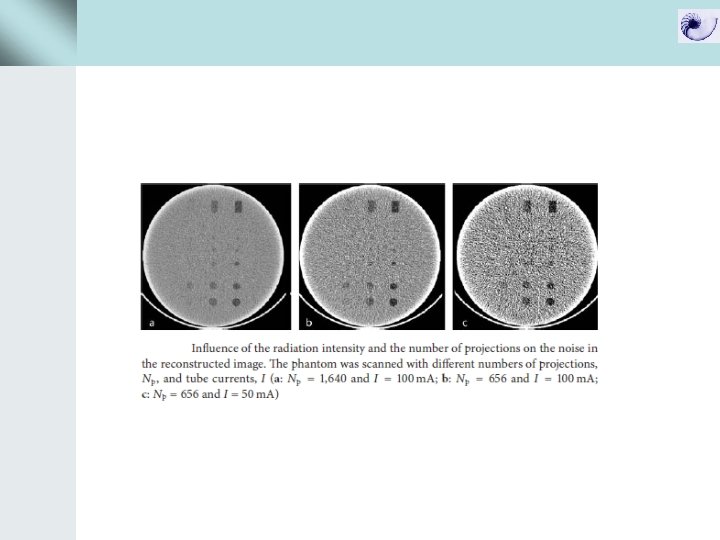

Pitch